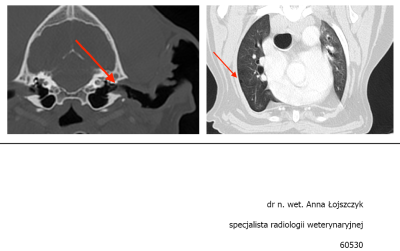

Maxiu jest po pełnej diagnostyce.

Zmiana okazała się włókniakomięsakiem :cry:

Aktualnie nie tracimy czasu i Maks przyjmuje chemię metronomiczną. Do tego rozważamy operację, którą zalecił chirurg onkolog Anna Rajska Krysa z przychodni Bemowo Wet - tam robiliśmy wszystkie badania i tam są w miarę dostępne terminy jesli chodzi o wizyty, dlatego zdecydowaliśmy się na leczenie w tym miejscu.

Nie jesteśmy jeszcze zapisani na zabieg ponieważ taka operacja to duże ryzyko dla psa w tym wieku, w dodatku umiejscowienie guza jest dość kłopotliwe, bo chirurg na pewno będzie musiał zachować margines przy wycięciu i usunąć część kości z nosa :( i szukam oczywiście jeszcze innych opcji i miałam nadzieję, że jest inny sposób, ale wygląda na to, że niestety operacja jest nieunikniona.

Obraz TK 1.jpg

Plik ściągnięto 6 raz(y) 29.5 KB

Obraz TK 2.PNG

Plik ściągnięto 7 raz(y) 344.31 KB